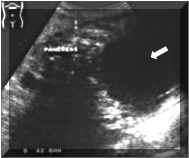

Pictures

1

and

2.